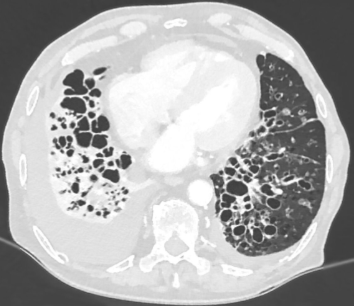

CF: CXR and CT

Air trapping and hyperinflation

Bronchiectasis